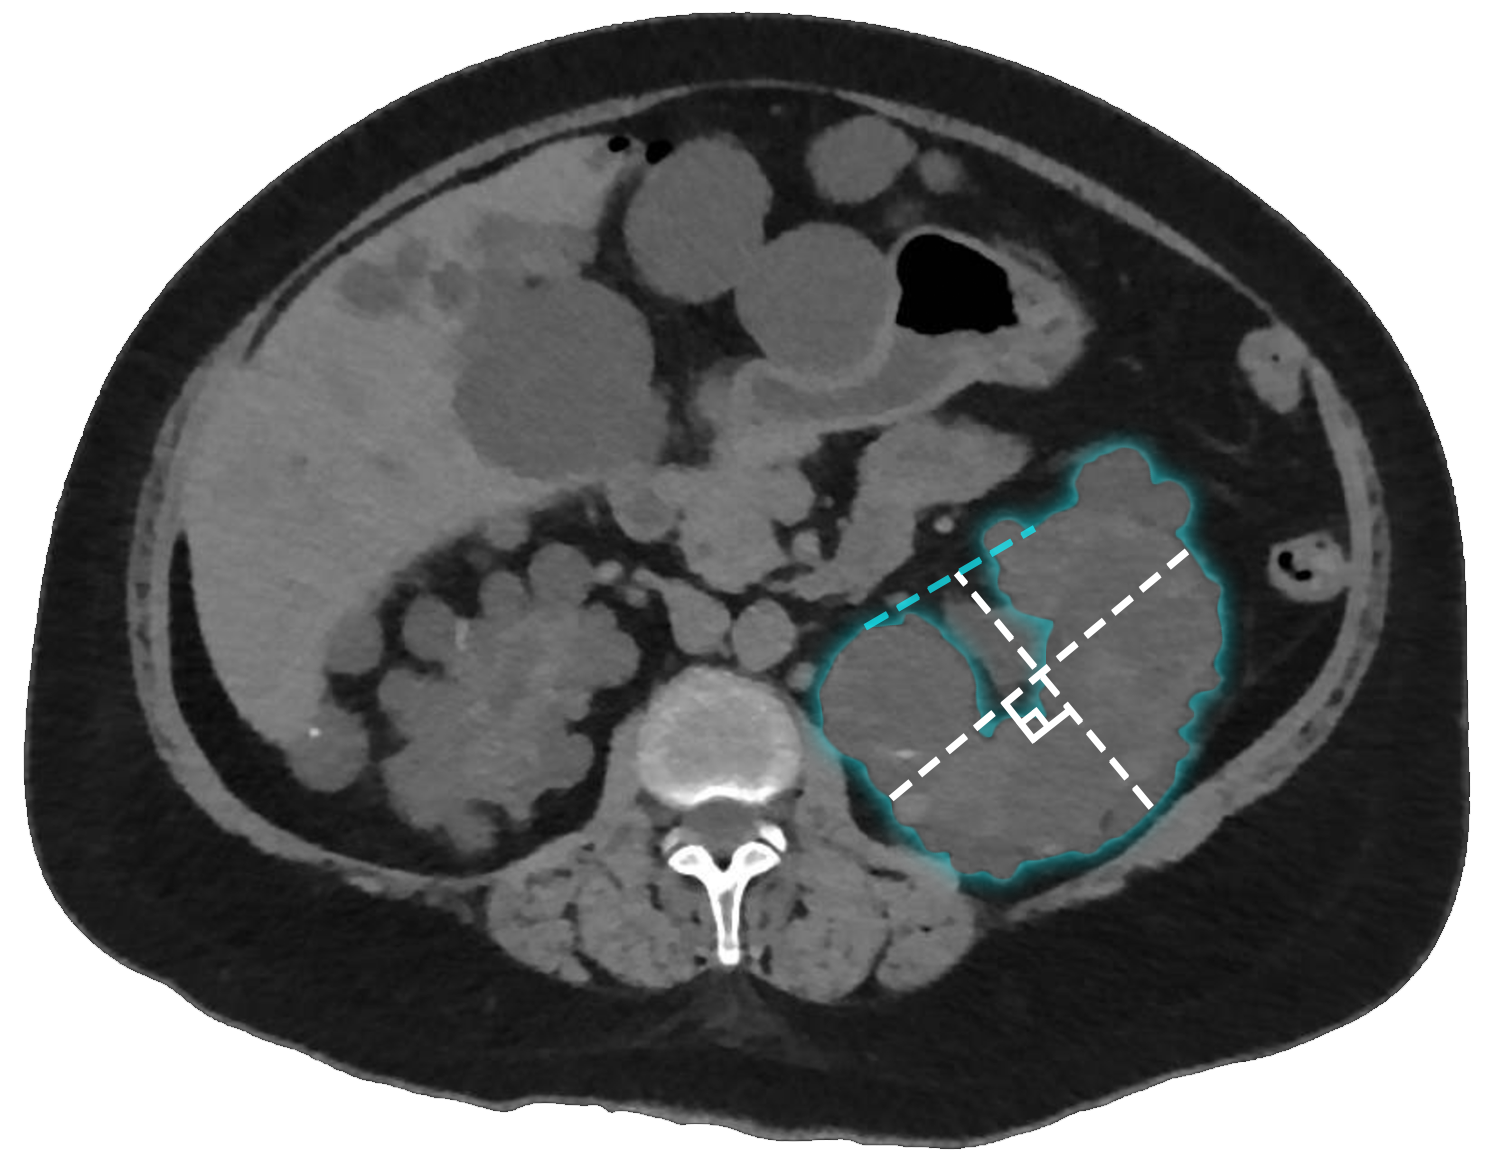

Kidney width

Measure the width along the axial axis using a line at 90° to the depth measurement line, positioned at the level of the renal hilum. Extend the measurement to an imaginary line that continues the renal border at the level of the hilum (dashed blue line). Ensure the line traces the edge of the renal parenchyma, excluding the outline of any protruding cysts